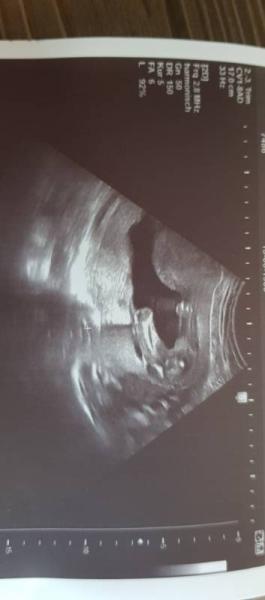

Hallo ihr lieben Murmeln endlich hatten wir heute nach 4 langen Wochen wieder einen FA Termin. Erst wollte Sie kein US machen, da der erst nächstes mal dran wäre aaaaber so lieb wie ich gefragt habe, konnte Sie nicht nein sagen ich wollte ja nun doch endlich mal wissen was wir bekommen und ob soweit alles okay ist. Obwohl ich Krümel ja doch jeden Tag schon spüre Also so wie es aussieht bekommen wir eine Prinzessin ohhhhh da kann das Shoppen doch beginnen. Bildchen gab es auch ...ich muss sagen das ich sehr Happy bin zu Team Rosa zu gehören. So nun allen einen guten Start ins Wochenende ich muss leider heute und morgen noch Arbeiten

Bild zu Endlich wieder FA Termin mit Outing - Forum für Januar - Mamis